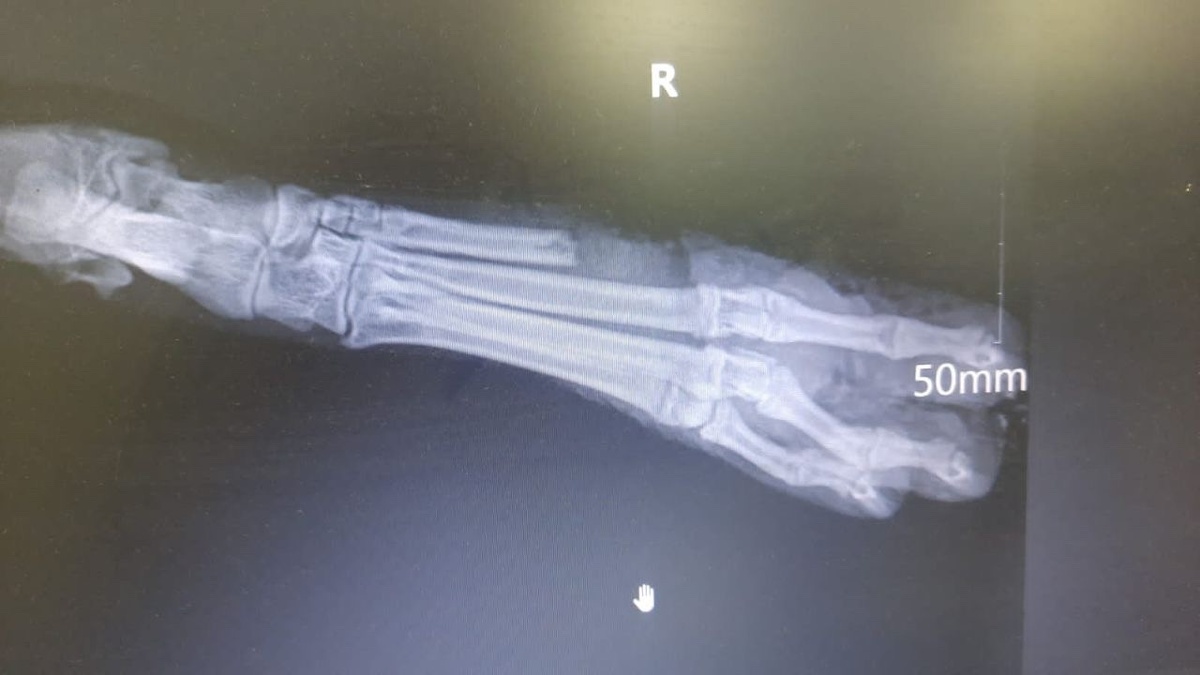

Но то ли в клинике плохо обработали, то ли девушка неопытная, не достаточно тщательно обрабатывала, но лапа стала гно'ить'ся и на повторном приеме врач предложил ампутацию! Рана сильно инфицирована и сломаны пальчики.